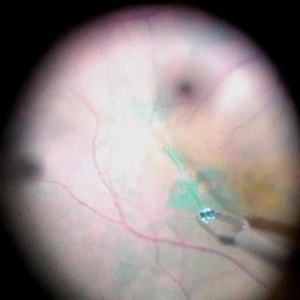

ILM Staining

Dec 11 2019 by Jennifer R Gallagher, MD

Intra-operative photo of the injection of indocyanine green (ICG) to stain the internal limiting membrane (ILM).

Photographer: Hamzah Khalaf, UT Health San Antonio, University Hospital

Condition/keywords: ILM staining, internal limiting membrane (ILM) peeling, surgical management